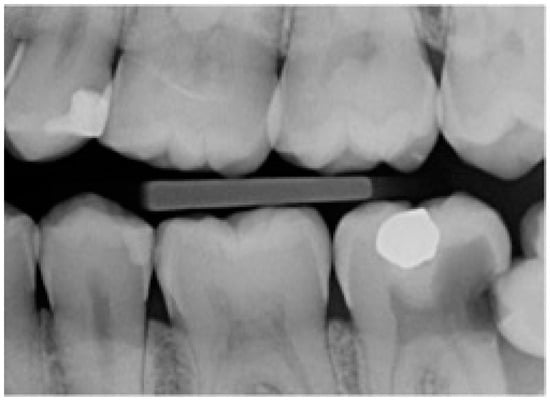

In this study, partial emergence or partial eruption of the mandibular third molar was determined by assessing the position of the third molar in relation to that of the adjacent mandibular second molar. Figure 1 illustrates a partially erupted mandibular and impacted third molar as seen on a bitewing radiograph, while Figure 2 illustrates a panoramic tomograph of a mandibular third molar that was deemed to be partially erupted. We judged the partial eruption of the third molar from the cusp levels; the third molars were deemed to be partially emerged when one of the cusps was positioned above the occlusal plane level or above the external oblique ridge. In cases in which these anatomical landmarks were not visible on the radiograph, the cementoenamel junction (CEJ) of the adjacent second molar in relation to the position of the marginal ridge of the adjacent mandibular third molar was used to obtain information on the depth of the third molar and was used to judge its eruption status [12]. This assessment method is a modification of the original Pell and Gregory classification [13]. Classes IIIA, IB, IIB and IIIB of the original Pell and Gregory categorization were included, thus excluding fully erupted potentially functional and fully impacted third molars. This classification (Figure 3) was applied to all third molar impaction types such as mesial, horizontal, distal, vertical and transverse.

Figure 1. Left bitewing radiograph of a partially erupted and impacted mandibular third molar.